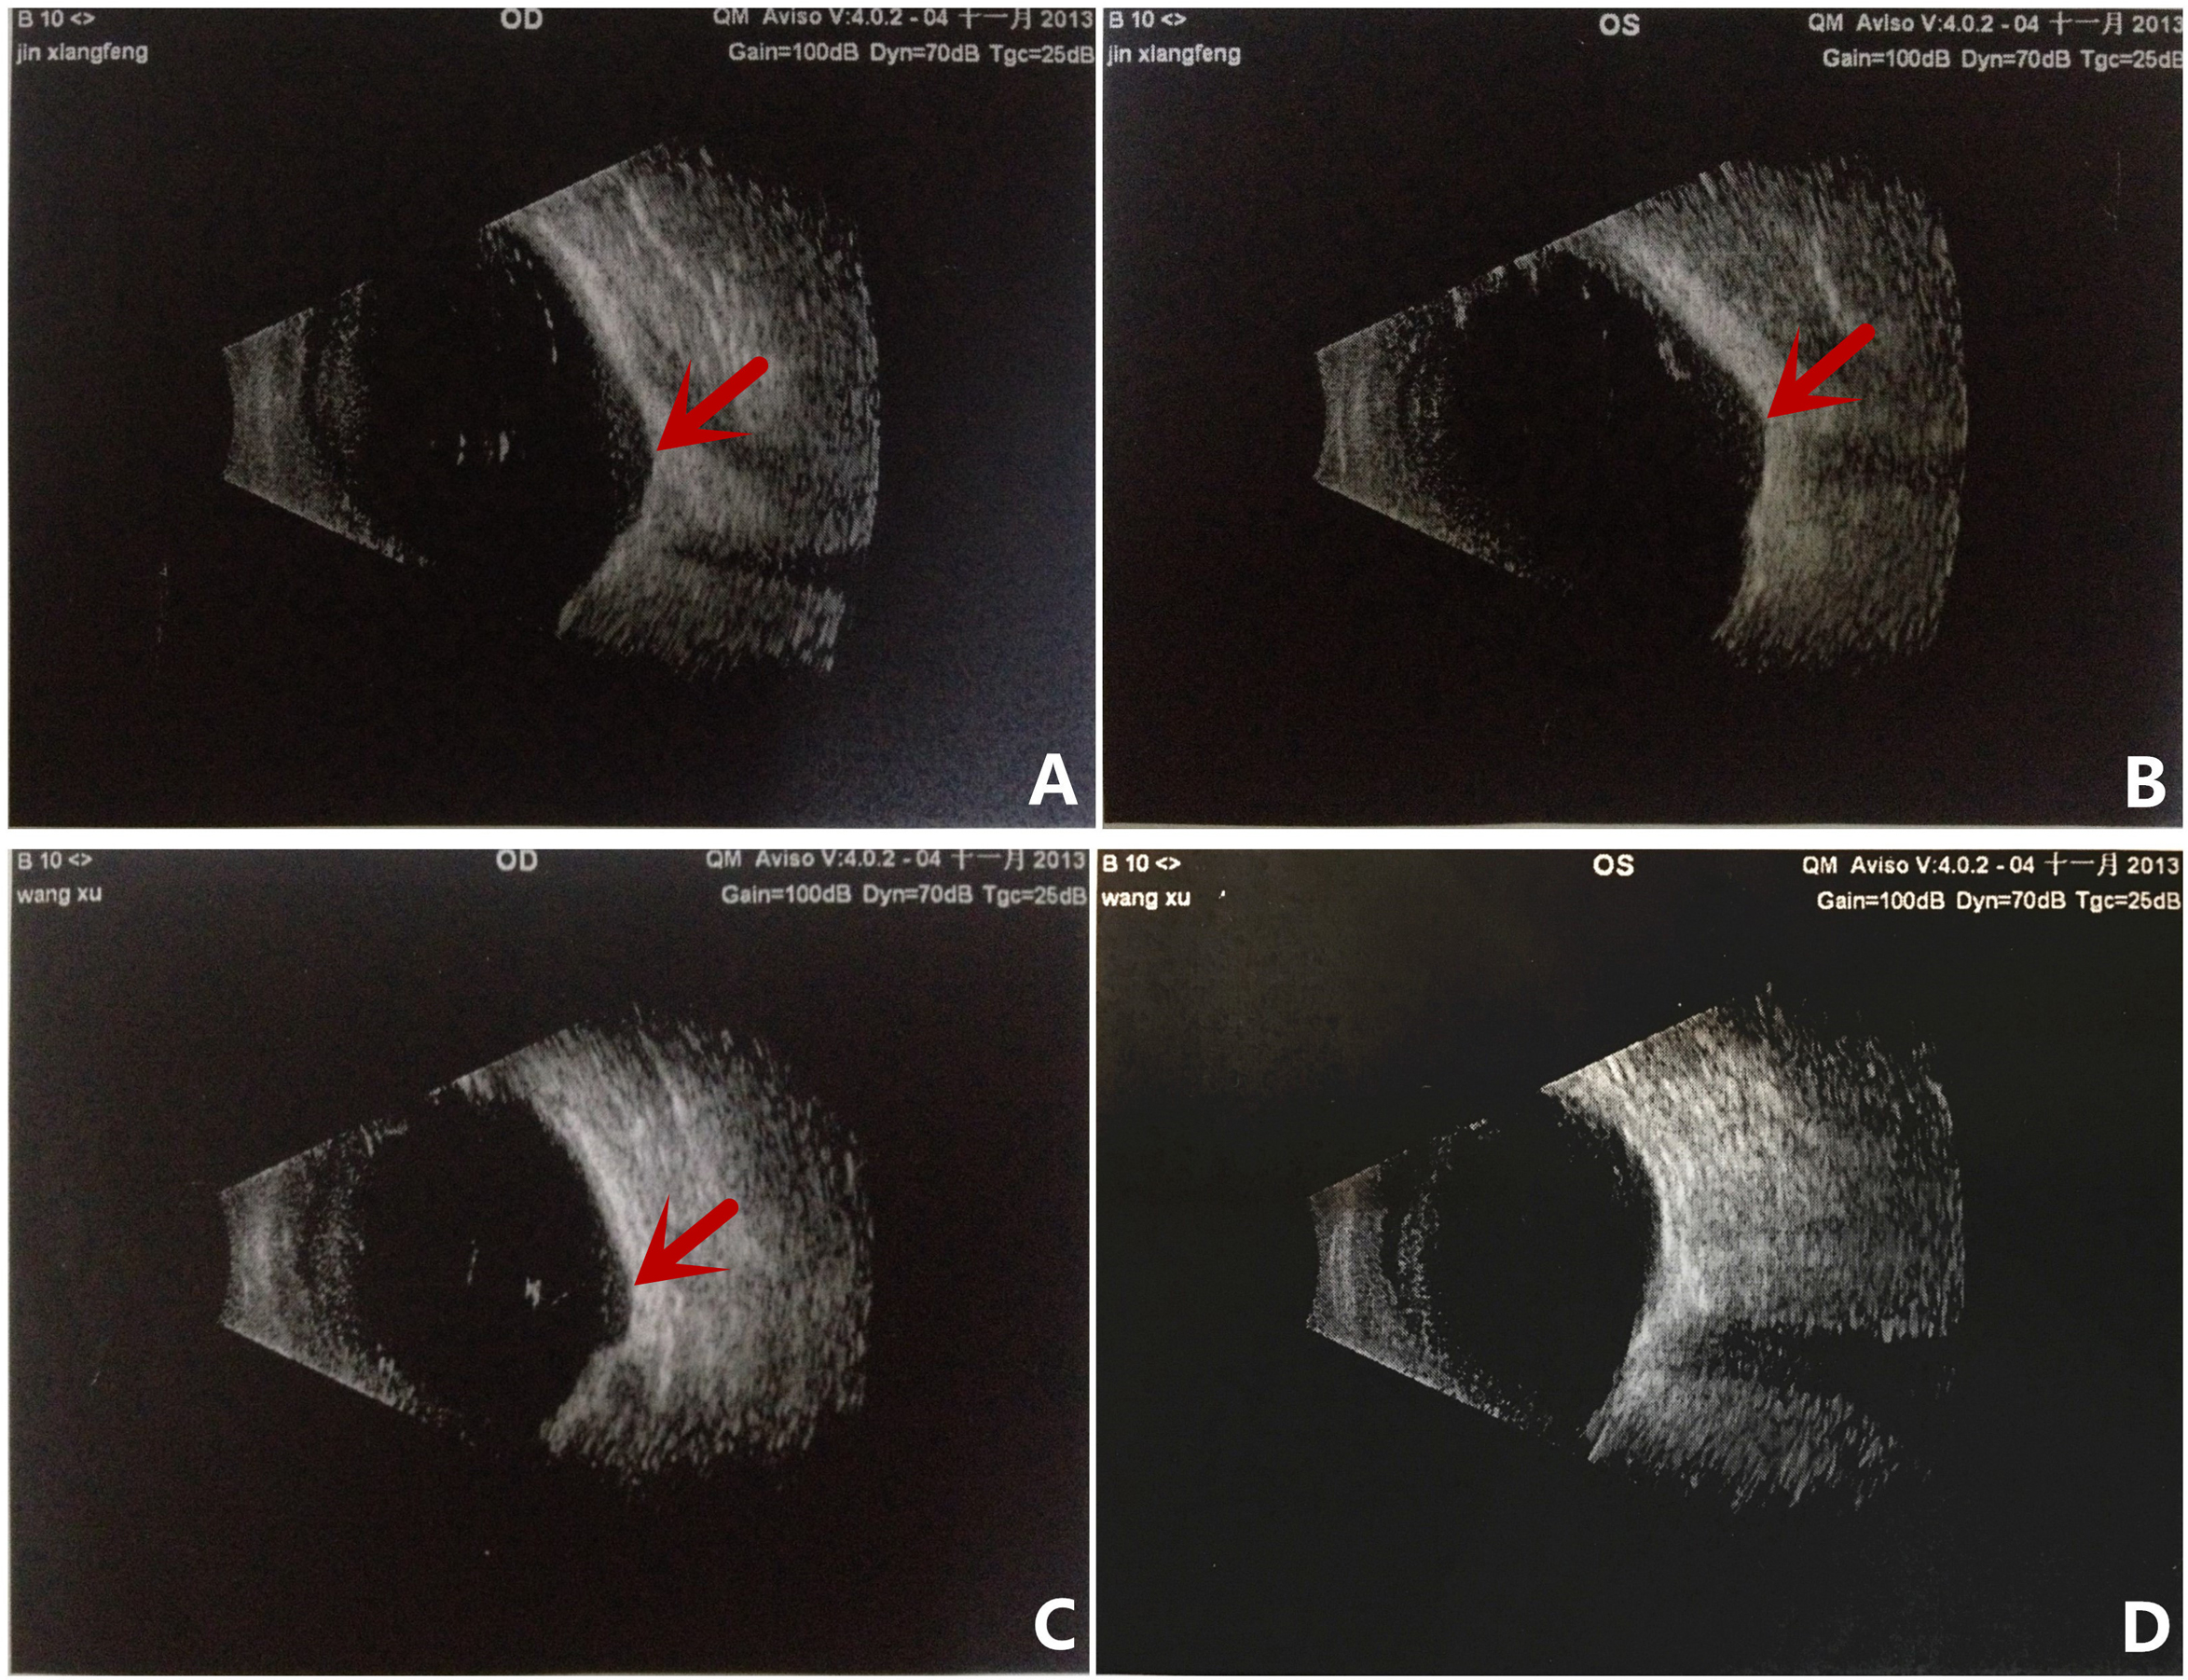

Figure 3. B-ultrasonography images of patients from family B. A and B: Images of the right and left eyes, respectively of patient II:2. C and D: Images of the right and left eyes, respectively, of patient III:1. The B-ultrasonography images show posterior segment coloboma

for both eyes of patient II:2 and the right eye of patient III:1. Focal and irregular introcessions in the eyeball wall are

marked with red arrows.